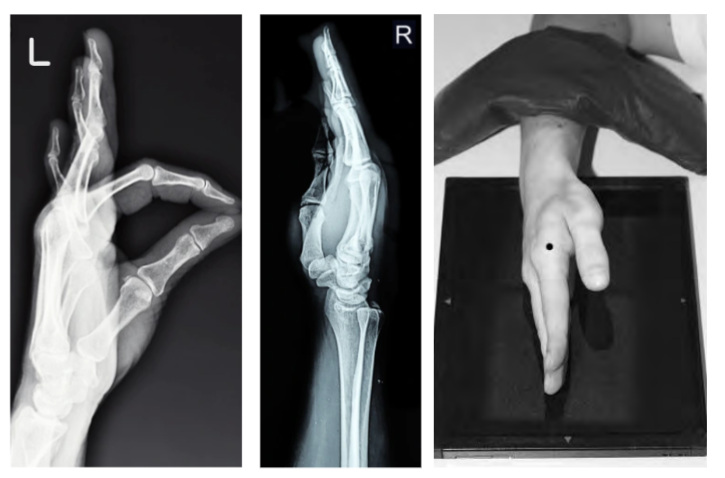

3. Lateral Hand X-ray

- Purpose: Evaluate displacement of fractures and foreign bodies.

- Positioning Steps:

- Position the hand in a “karate chop” pose (ulnar aspect against the IR).

- Fan the fingers to separate the phalanges for a lateral projection of each digit.

- Align the CR perpendicular to the second MCP joint.

- Key Consideration: A true lateral position ensures superimposition of metacarpals and proper visualization of soft tissues.